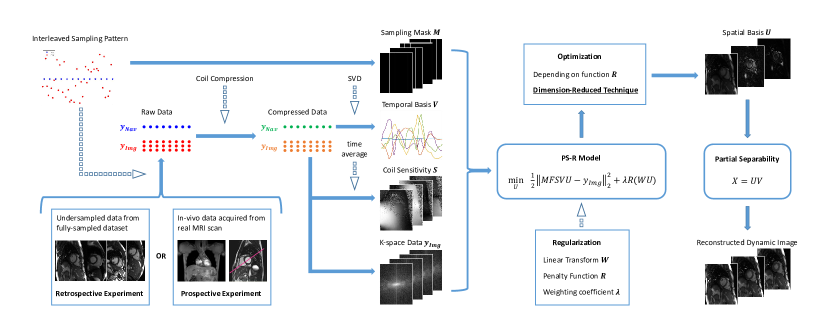

The data acquisition of PS model is divided into two parts, as illustrated in Figure 1. “Navigating data” samples the center region of k-space at high temporal resolution, while “Imaging data” slowly samples the whole k-space. The two parts of data are sampled in an interleaved fashion. A two-step framework is adopted for image reconstruction. First, singular value decomposition (SVD) is performed on and the first singular vectors are extracted as . Second, is assumed to be fixed, is calculated by minimizing the noise energy:

4.2 Reconstruction Pipeline

An image reconstruction pipeline is established to provide a fair platform for algorithm comparison, as shown in Figure 2. Simulation data and in-vivo data are both reconstructed by this pipeline. Firstly, input data is undersampled according to the interleaved pattern. Afterwards, the coil channel number is reduced to 6 by GCC coil compression method[54]. Then, the data is normalized by its maximum magnitude. Then, SVD is performed on “Navigating data” to extract temporal basis functions . “Imaging data” is averaged along the time dimension and used for estimating coil sensitivity maps . Undersampling mask and k-space data are also calculated from the “Imaging data”. The regularization term and optimization algorithm are designed independently for different PS models, as described in Section III. When the solution is obtained, the dynamic images are calculated by . All the computations were performed in MATLAB (The MathWorks, Natick, MA) in a personal computer equipped with 96 GB RAM and an Intel i9-10900F CPU.